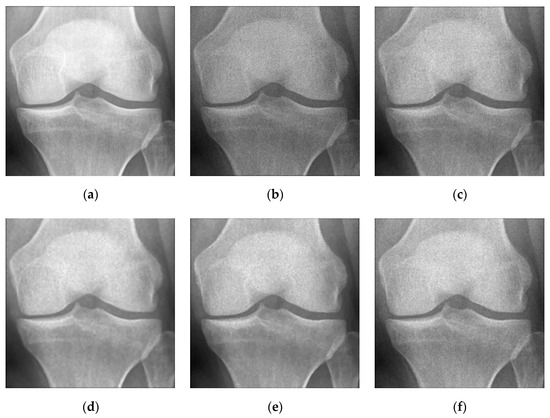

5.2. Numerical Simulations on Medical Images

5.2.2. Different Methods

- ADMM Method

5.2.3. Comparison with Other Variational Models